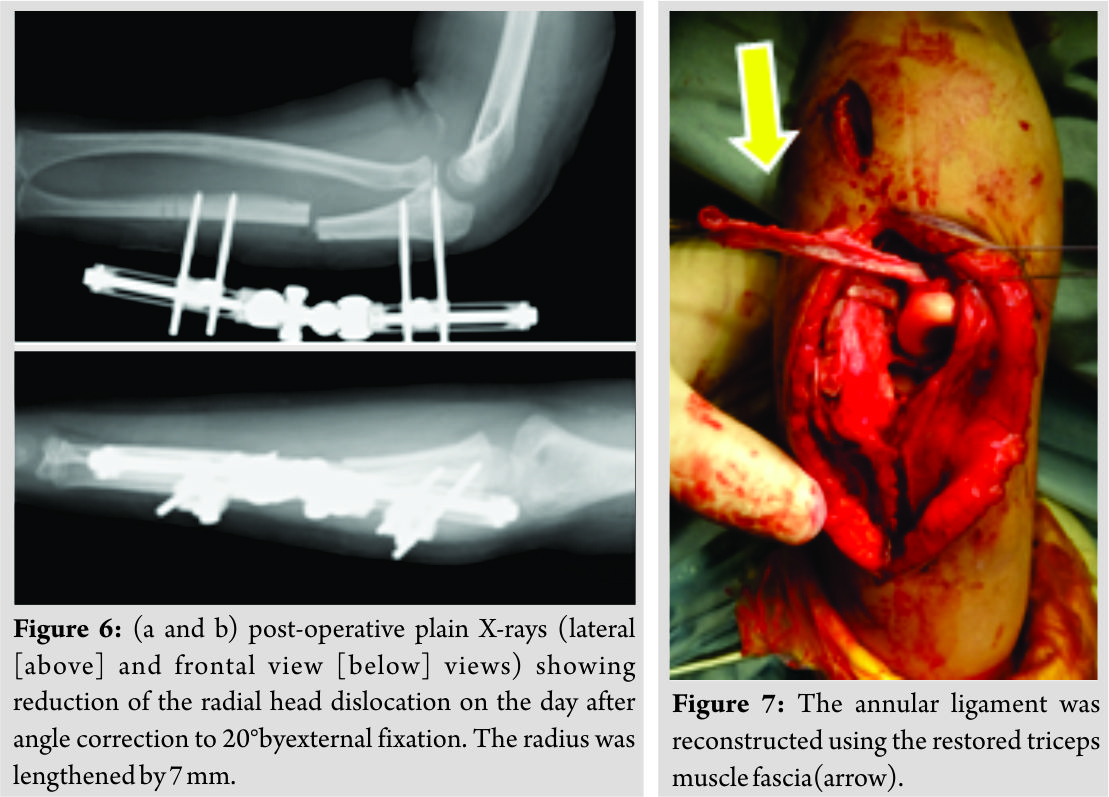

It was important to remove the scar tissue surrounding the radial head.

Case Report: A 6-year-old girl who was injured by a fall was examined by a local physician. 4 weeks later, she was referred to our hospital. Plain X-ray and computed tomography revealed a long-standing Monteggia fracture. Ulnar osteotomy was performed; however, complete realignment was not achieved. Scar tissue and the annular ligament remained intact, thereby hindering complete reduction. The scar tissue surrounding the radial head was surgically removed, and subluxation was reduced. The annular ligament was reconstructed, and the ulna was lengthened by external fixation. 1 year postoperatively, the patient’s elbow range of motion is good, and there has been no recurrence of radial head dislocation.

The scar tissue and annular ligament remained intact, thereby hindering complete reduction (Fig. 5). The subluxation was reduced after surgically removing the scar tissue surrounding the radial head. The annular ligament was reconstructed using the Bell-Tawse method. Thereafter, 8 mm × 75 mm of the triceps muscle fascia was restored. To prevent obstruction of the triceps muscle fascia, two half-pins were inserted in the proximal and distal ulna, respectively. External fixation was performed using an Orthofix external fixator (M511). The correction angle was set at 20° (Fig. 6 and 7).

In our patient, the scar tissue and annular ligament remained intact, hindering complete reduction, which was not achieved despite performing ulnar osteotomy and straightening. Further, we believe that the good post-operative progress was achieved and post-operative repeat dislocation was avoided by reducing radial head dislocation, removing the scar tissue, and reconstructing the annular ligament.

We performed ulnar osteotomy and straightening, bone lengthening, and annular ligament reconstruction for a long-standing Monteggia fracture. While ulnar osteotomy and straightening are the basic treatment, it is important to remove the scar tissue from the site of the radial head.

In case of chronic anterior Monteggia lesions, the remainder of the annular ligament and the scar tissue became an obstacle to the reduction of the radial head. It was important to remove the scar tissue surrounding the radial head.